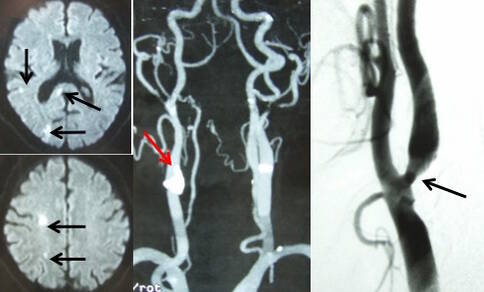

右颈颈动脉狭窄引起的脑梗塞,图源:东京女子医科大学